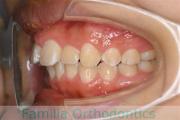

No.22V-220

- 上顎前突

- 叢生

- 23歳

- 男性

- 上:

- 448

- 下:

- 主な使用装置:

- FEA 022

- 治療にかかった費用:

- 88万円

歯並びをきれいにしたいということで来院されました。非常に強い前歯の突出と叢生(でこぼこ)でした。上下左右から小臼歯を抜歯してマルチブラケット法にて治療を行いました。前歯の歯根が短く、歯根吸収のリスクが非常に高いケースでした。前歯に負担をかけないように3年弱、30回程度の通院で治療を行いました。

- ≫治療前

- ≫治療後